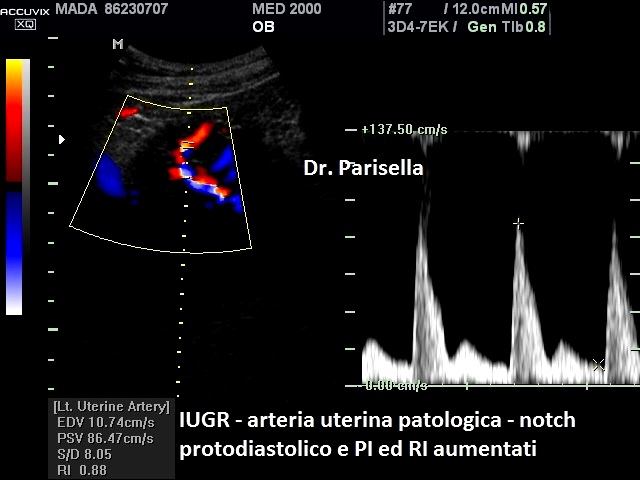

Arterie Uterine e Arterie Ombelicali - La flussimetria delle arterie uterine ha validità prevalente tra la 20a e la 24a settimana di gestazione (RCOG Green-top Guideline No. 31). Nel primo trimestre di gravidanza quando le arterie spirali invadono il trofoblasto le arterie uterine passano da vasi ad alta resistenza a vasi a bassa resistenza con conseguente aumento del flusso sanguigno; ciò permette di stabilire un flusso a bassa resistenza adeguato alla perfusione della placenta. Se questo processo, che si completa intorno alla 20° settimana di gestazione, non si verifica normalmente la mancata trasformazione delle arterie uterine da vasi ad alta resistenza in vasi a bassa resistenza condiziona una inadeguata invasione trofoblastica delle arterie spirali con conseguente circolazione ad alta resistenza ed aumento del PI nelle arterie uterine. In presenza di un difetto di crescita la persistenza di un PI medio delle arterie uterine elevato (PI medio > 95° percentile per epoca gestazionale) è associata a insufficienza placentare ( Levytska K et al., 2017 ). La eventuale successiva normalizzazione degli indici di velocità di flusso risulterà ancora associata ad un aumentato rischio di neonato FGR (RCOG Green-top Guideline No. 31). L’aumento del PI nelle arterie uterine provoca un aumento delle resistenze nella vascolarizzazione placentare con conseguente riduzione della superficie placentare disponibile per lo scambio di ossigeno e nutrienti (Burton GJ et al., 2019) cui segue un progressivo aumento del PI nelle arterie ombelicali (UAPI). Nel Feto il primo cambiamento emodinamico è una riduzione del flusso venoso ombelicale con conseguente ridistribuzione del flusso venoso dal fegato al cuore fetale, le dimensioni del fegato diminuiscono causando un ritardo di crescita della circonferenza addominale fetale che è il primo segno biometrico di Feto FGR. L’insufficienza vascolare placentare, inizialmente caratterizzata dall’aumento del UAPI, può peggiorare passando, nella fase terminale, da un flusso diastolico ridotto in arteria ombelicale (PED) ad un flusso assente (AED) o invertito (RED). L'assenza e/o la inversione del flusso telediastolico (ARED: absent or reverse end-diastolic flow) nelle arterie ombelicali è un segno importante di compromissione sia fetale che placentare rappresentando un importante predittore di danno cerebrale o di morte neonatale nei feti FGR.

Arterie Uterine (UtA) La velocimetria Doppler delle arterie uterine nel I trimestre può essere utilizzata insieme ai marcatori biochimici nell’ambito di un test multiparametrico per lo screening della patologia ipertensiva della gravidanza e del ritardo di crescita intrauterino nella popolazione generale e nella popolazione ad alto rischio. In questo studio del 2017 sullo screening della preeclampsia e ritardo di crescita nel I trimestre la velocimetria Doppler delle arterie uterine associata al dosaggio sierico della PAPP-A e del fattore di crescita placentare (PlGF) ha dimostrato una sensibilità superiore al 75% con un 10% di falsi positivi (Rolnik, 2017). Tale test presenta una sensibilità e una specificità maggiore rispetto al dato anamnestico e potrebbe essere di aiuto nell'identificare la migliore strategia preventiva. La velocimetria Doppler delle arterie uterine nel II trimestre è raccomandata per la predizione della preeclampsia e del ritardo di crescita intrauterino nelle pazienti ad ALTO rischio (Velauthar et al., 2019; Townsend et al., 2019). In queste pazienti (ALTO RISCHIO: Anamnesi di pregressa patologia ipertensiva della gravidanza, malattie autoimmuni quali lupus eritematoso sistemico (LES) e sindrome linfoproliferativa autoimmune (ALPS), precedente riscontro di neonato piccolo per epoca gestazionale o sospetto rallentamento della crescita fetale) la velocimetria Doppler consente di attuare un management clinico di stretta sorveglianza clinica finalizzata al miglioramento degli esiti clinici (Linee Guida SIEOG 2021).

Uno studio su gestanti a basso rischio (Myatt et al., 2012) ha dimostrato che le anomalie della velocimetria Doppler delle arterie uterine sono significativamente più frequenti nelle pazienti con preeclampsia con caratteristiche di severità (ipertensione severa >160/110 mmHg, proteinuria >5 g/24 ore, oliguria, edema polmonare, piastrinopenia, sindrome HELLP ed eclampsia). Un altro studio ha dimostrato che il riscontro di un indice di pulsatilità anomalo associato alla presenza di notch bilaterale rappresenta il più importante parametro predittivo di preeclampsia nelle pazienti ad alto rischio ma ha una minore accuratezza nell'identificazione delle pazienti a rischio che svilupperanno ritardo di crescita intrauterino (Cnossen et al., 2008). Un altro studio ha dimostrato un rischio di morte endouterina tre volte superiore nelle pazienti con anomalie della velocimetria Doppler delle arterie uterine nel II trimestre (Allen et al., 2016).